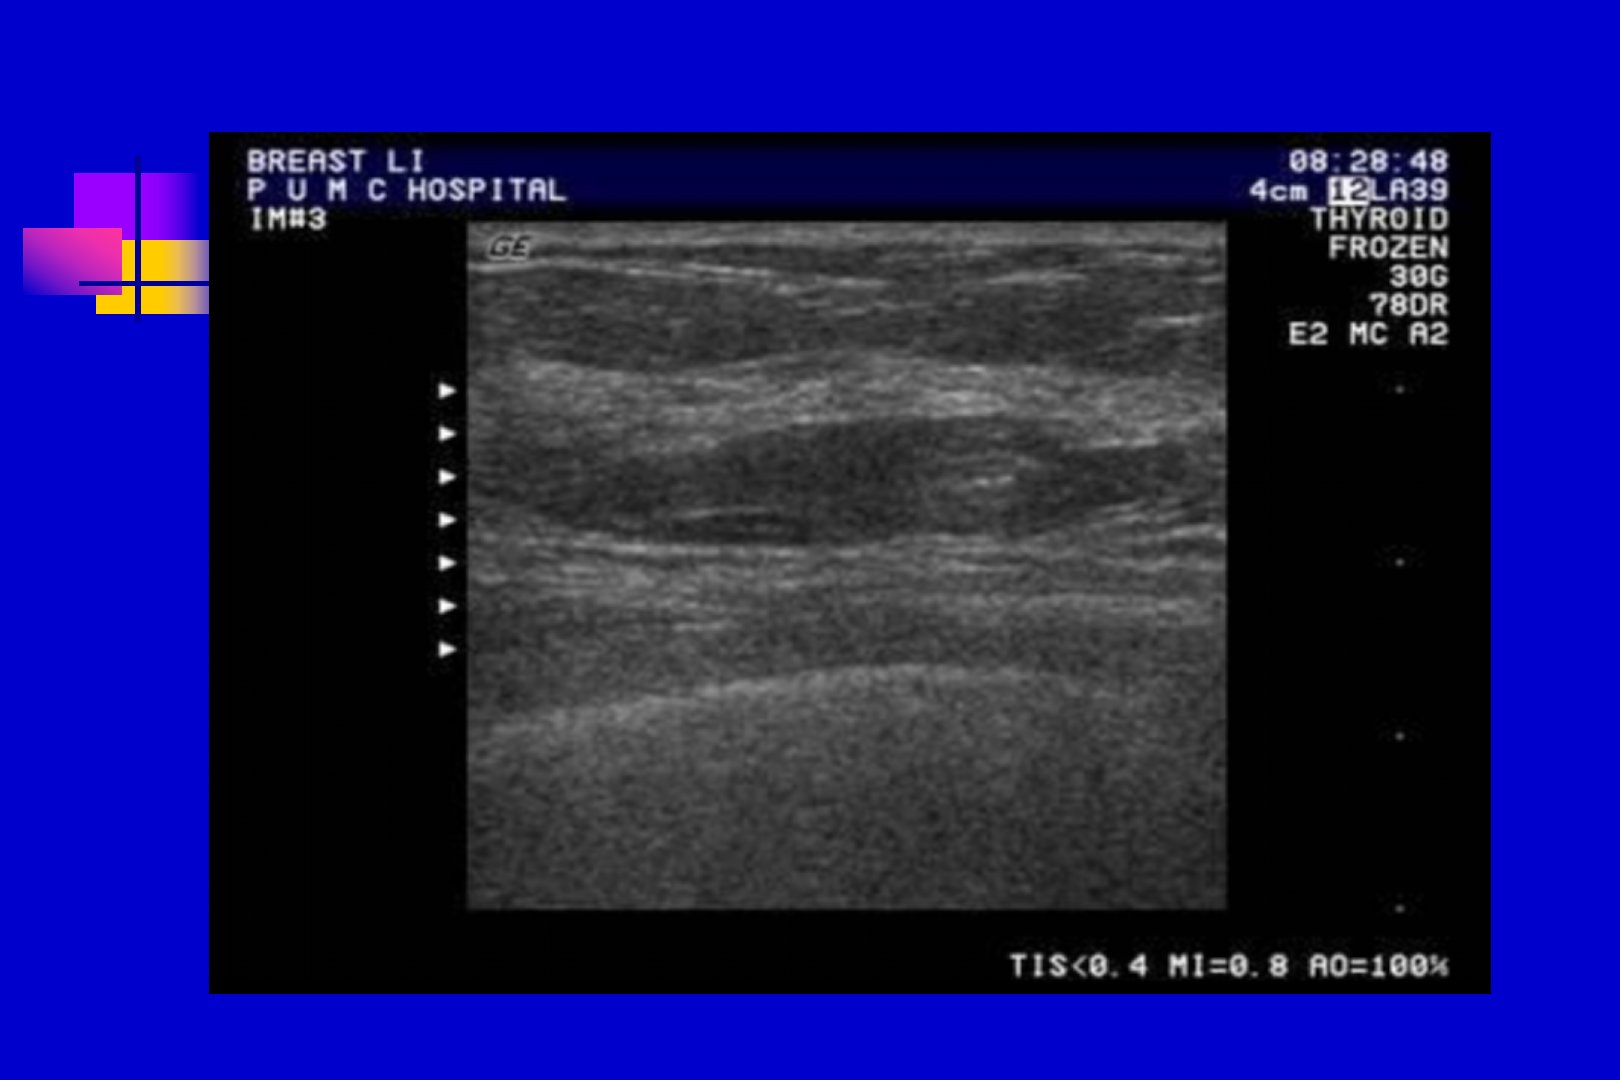

乳腺超声检查中解剖位置位于胸前第26肋骨间胸大肌浅面检查前需暴露乳房双手置于脑后常用75MHz宽频带线阵探头。正常乳房超声解剖分为四个区域回声因人而异随年龄而变化。检查时需注意不同生理状态下声像图的变化并与对侧比较尤其注意乳房边缘和腋窝部避免遗漏。乳腺囊性增生典型表现为月经前胀痛绝经后缓解与卵巢内分泌失调有关。典型乳腺囊肿形态为圆形或椭圆形边界清晰、规整壁薄呈环形中强回声内部为无回声区。急性乳腺炎多发生于哺乳期受累区腺体层增厚回声减低。导管内乳头状瘤多位于乳腺中心部血供丰富。乳腺纤维腺瘤、乳腺癌各有其病理与声像图特点乳腺癌边界不整、内部回声不均内部及周边血供丰富。乳腺增生结节与乳腺癌的超声鉴别有一定难度纤维腺瘤与乳腺癌的二维及彩超鉴别要点不同。小器官超声诊断中灰阶超声是重要诊断信息来源CDFI可提供有价值信息良性肿瘤边界多清晰规整恶性肿瘤则多不均质低回声、边界不清。